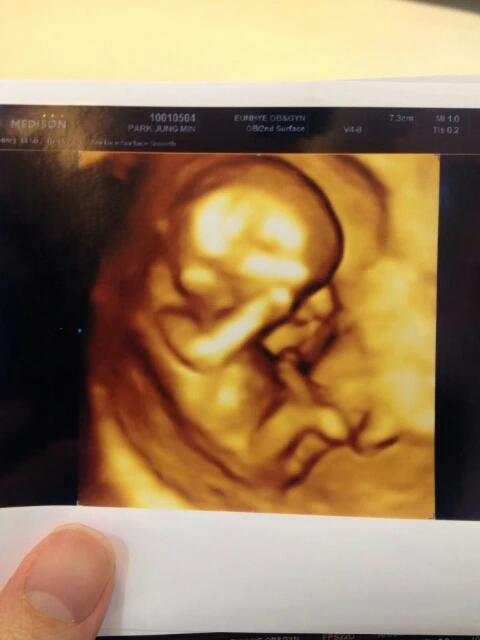

11주 4일 째 라미의 모습.

2주 전에 2.95cm이었는데 4.73cm이 되었네. 1.78 cm가 더 자랐네.

엄마는 라미의 '기형아 검사(1차)'를 하러 혼자 병원에 가서 이 사진을 보내줬단다.

잘 크고 있음은 물론이고 기형의 징후가 일단 없다고 하여(2차 검사까지 가봐야겠지만) 가슴을 쓸어내렸단다. 아빠는 라미가 혹시 '장애'를 갖고 태어날까봐 악몽까지 꾸는 밤들이 있거든.